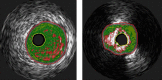

N-3 polyunsaturated fatty acids (PUFAs) are thought to have protective effects against cardiovascular disease. Here, we report the relationship between serum PUFA concentrations and plaque composition, as evaluated by virtual histology-intravascular ultrasound (VH-IVUS). Consecutive patients (n=61) who underwent percutaneous coronary intervention (PCI) were pre-operatively examined using VH-IVUS to assess the composition of culprit plaques. Gray-scale IVUS and VH-IVUS data of fibrous, fibro-fatty, necrotic core, and dense calcium regions of plaques were estimated at the minimal luminal area sites of culprit lesions. Serum levels of high-sensitivity C-reactive protein (hsCRP) and PUFAs, including eicosapentaenoic acid (EPA), docosahexaenoic acid (DHA), and arachidonic acid (AA), were compared between patients with (ACS, n=27) and without acute coronary syndrome (non-ACS, n=34) before PCI. Multiple logistic regression analysis of the data showed that EPA/AA under the median was more highly associated with ACS than hsCRP over the median. In addition, EPA/AA was negatively correlated with the percentage of fibrous plaque regions and EPA/AA and DHA/AA were positively correlated with the percentage of dense calcium regions in plaques. Furthermore, the correlation index of EPA/AA was the most highly (R=0.513) correlated with the percentage of dense calcium regions in plaques.